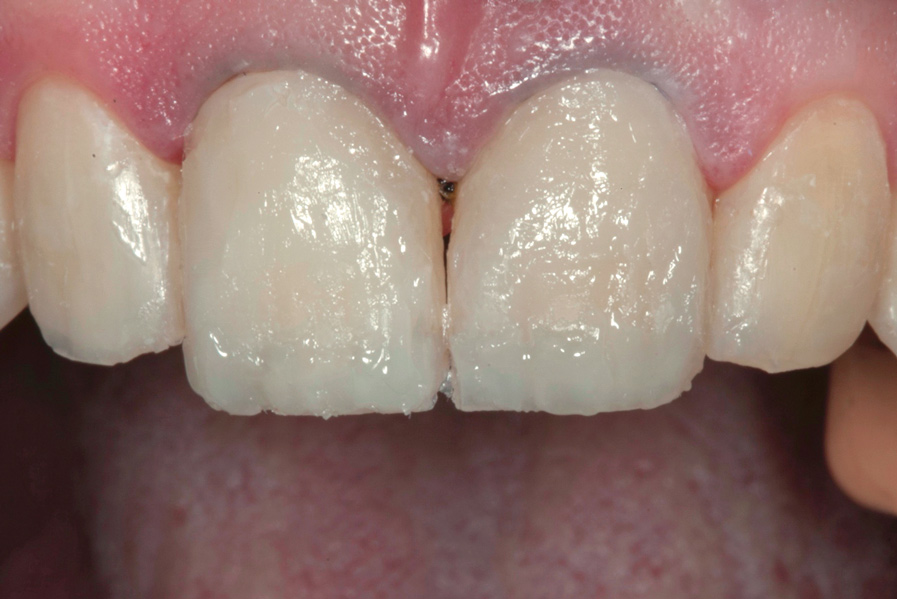

(10.) Postoperative smile photograph.

Figure 10

(12.) Postoperative upper anterior view.

Figure 12